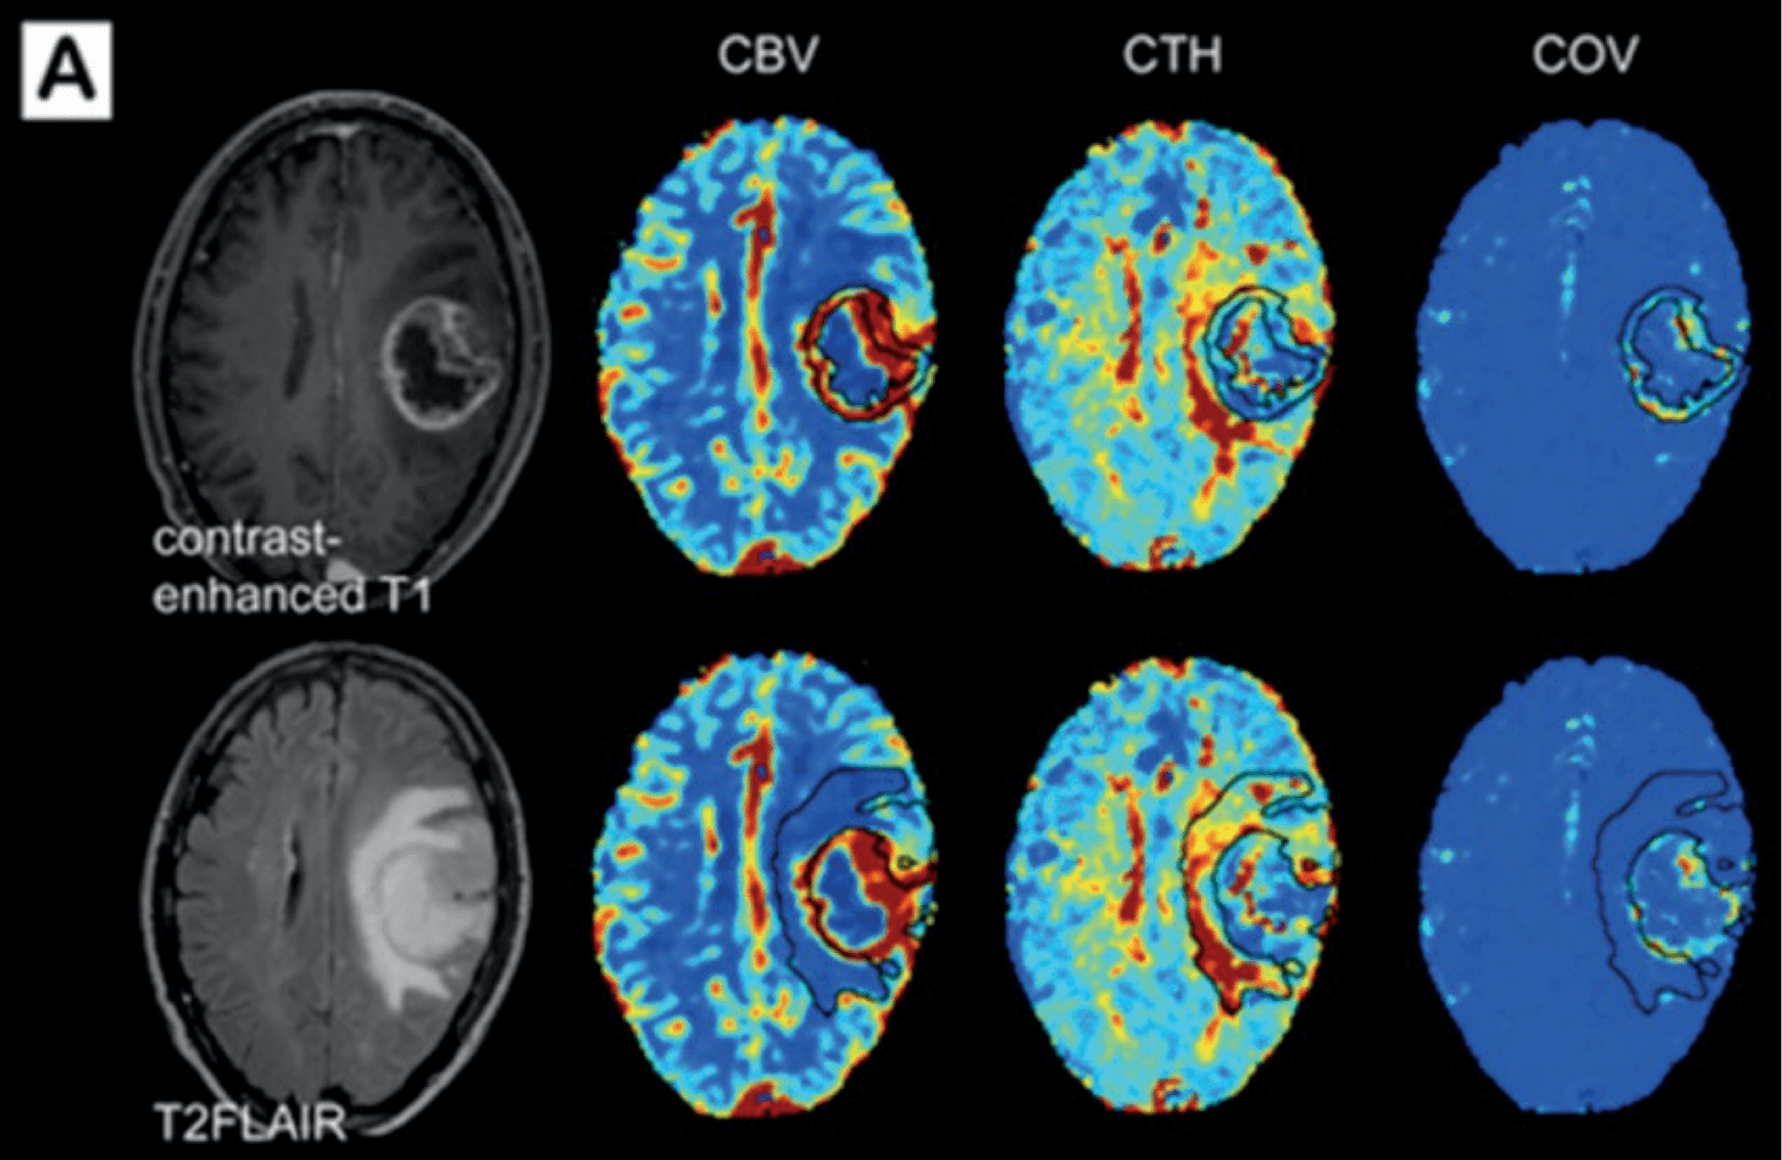

ONCOLOGIA- Imaging Metabolico e Perfusionale Avanzato

Nelle patologie oncologiche cerebrali, una caratterizzazione accurata della lesione è essenziale per stabilire aggressività, trattamento e prognosi.

Le sfide dell’imaging oncologico

- Difficoltà nel distinguere progressione tumorale da pseudoprogressione.

- Necessità di una valutazione combinata vascolare + metabolica.

- Parametri tradizionali spesso insufficienti.

BIOMARCATORI PROPRIETARI PER LA NEURO-ONCOLOGIA

Biomarcatori Vascolari

- CTH Eterogeneità del tempo di transito capillare.

- COV Coefficiente di varianza microvascolare.

- Leakage Integrità della barriera emato-encefalica.